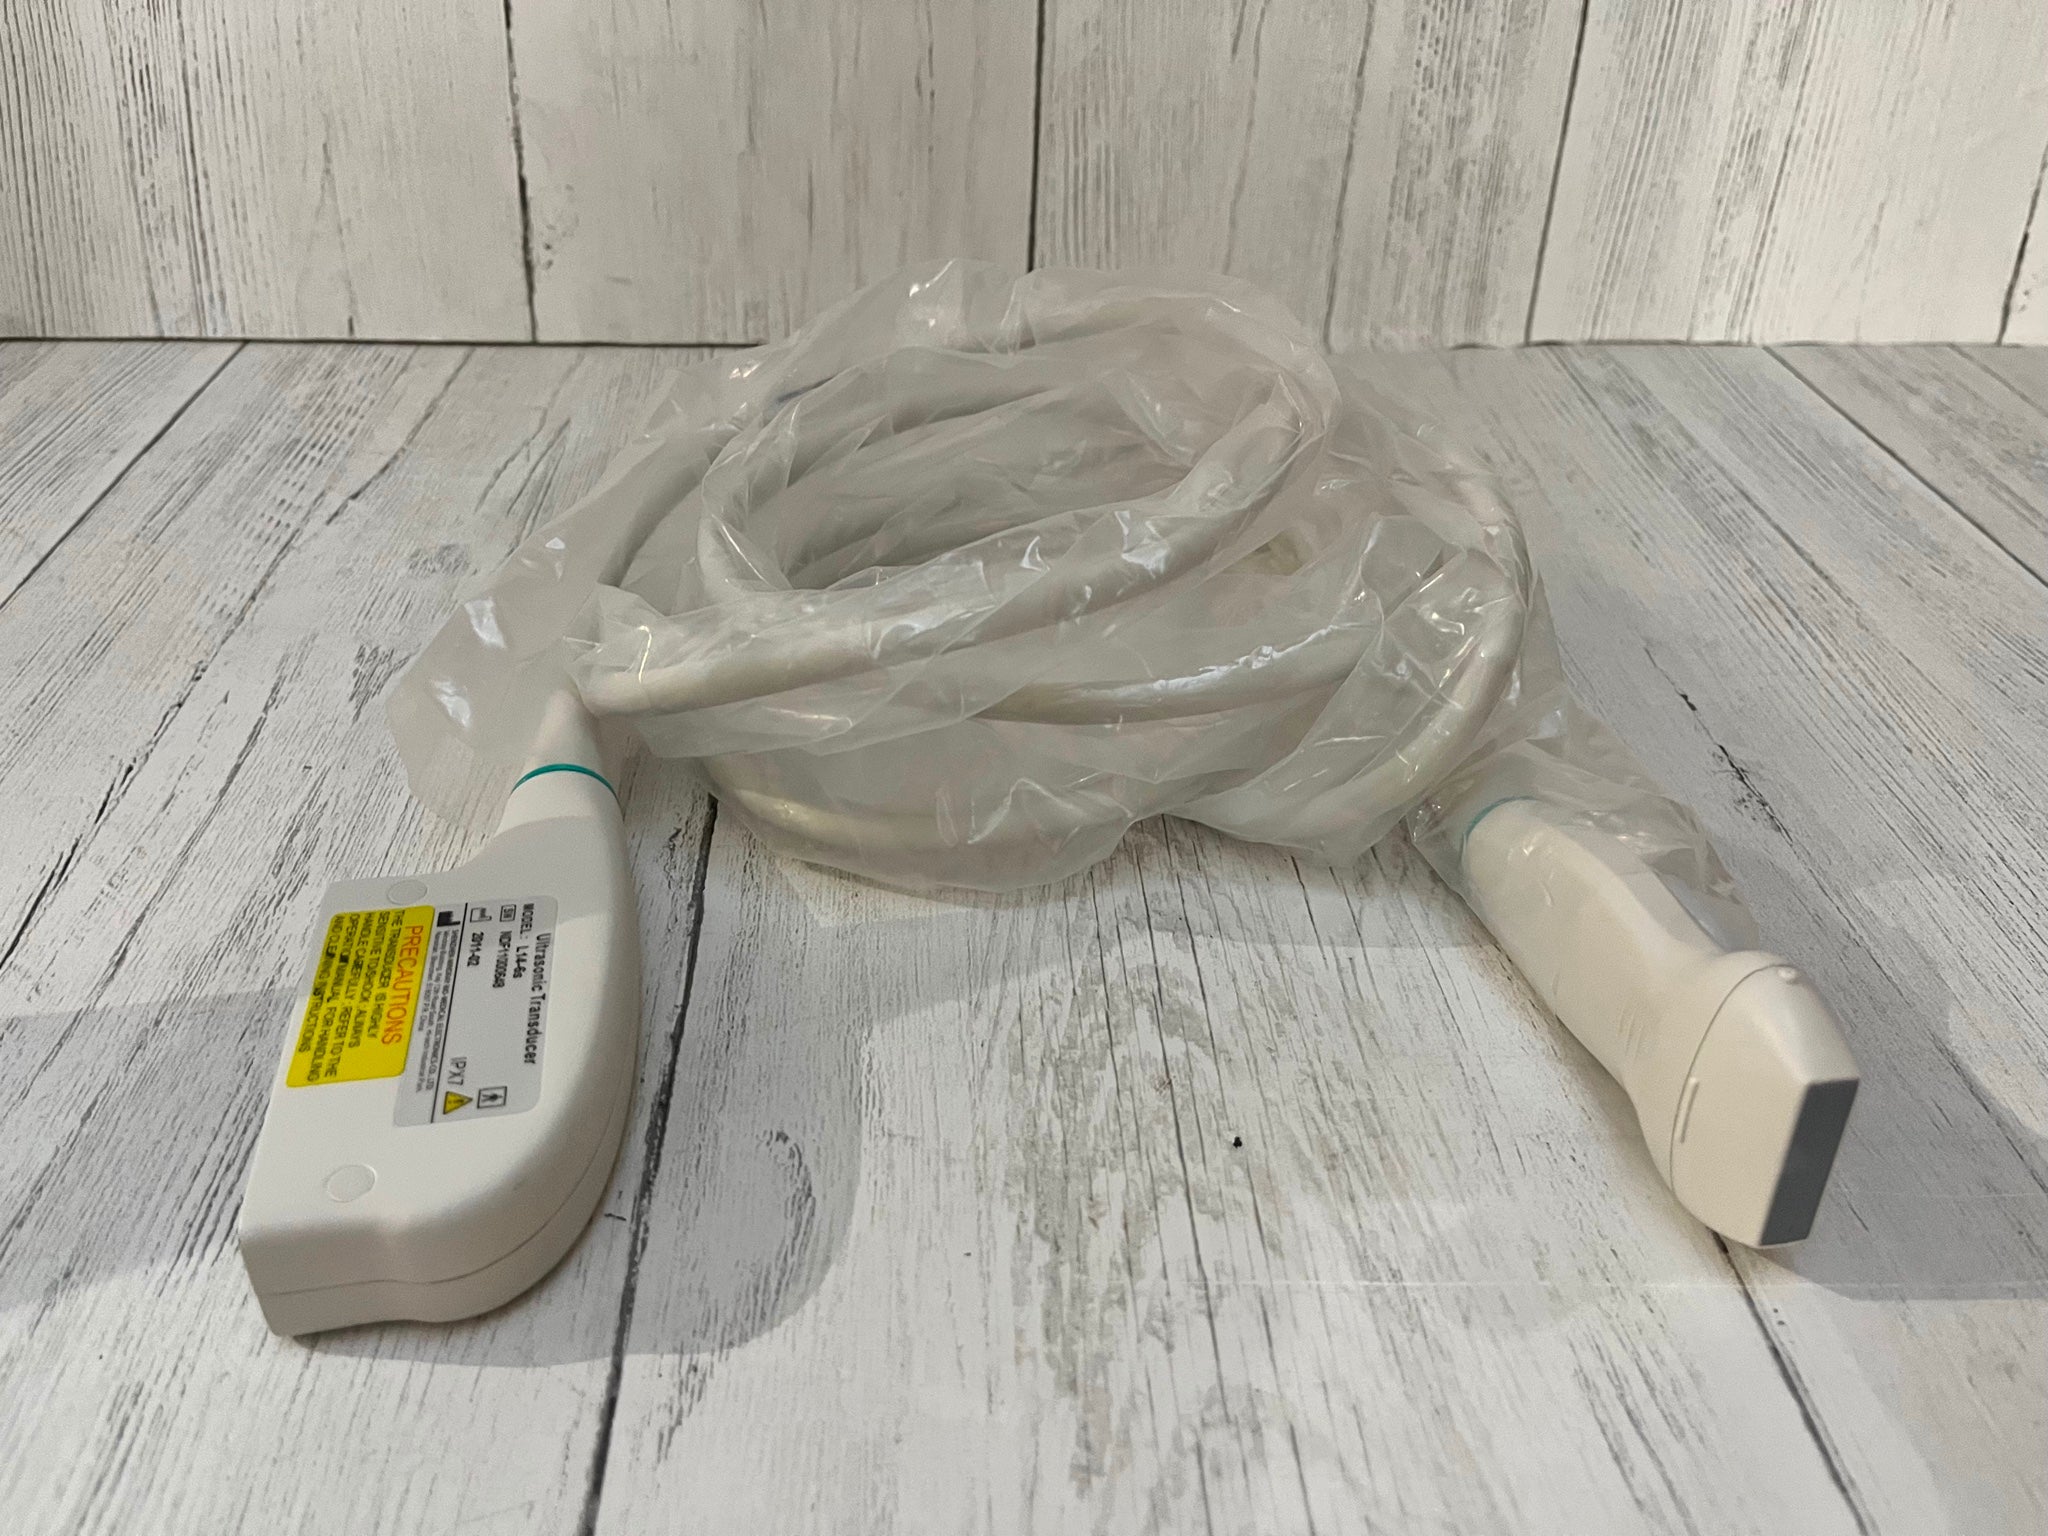

The CE Digital Laptop Ultrasound Scanner is designed to provide high-quality imaging for medical professionals. With its advanced 7.5MHz linear probe, this scanner captures clear and precise images, allowing for accurate diagnostics. It is especially beneficial for procedures requiring detailed visualization, such as vascular and musculoskeletal examinations. This tool empowers healthcare providers, so they can deliver better patient care through enhanced imaging technology.

This laptop ultrasound scanner is lightweight and compact, making it highly portable. Doctors can easily transport it between rooms or different facilities, ensuring they always have access to essential diagnostic tools. Furthermore, its user-friendly interface allows even those with limited ultrasound experience to operate it effectively. Therefore, healthcare professionals can quickly adapt and integrate it into their daily practices, maximizing efficiency.